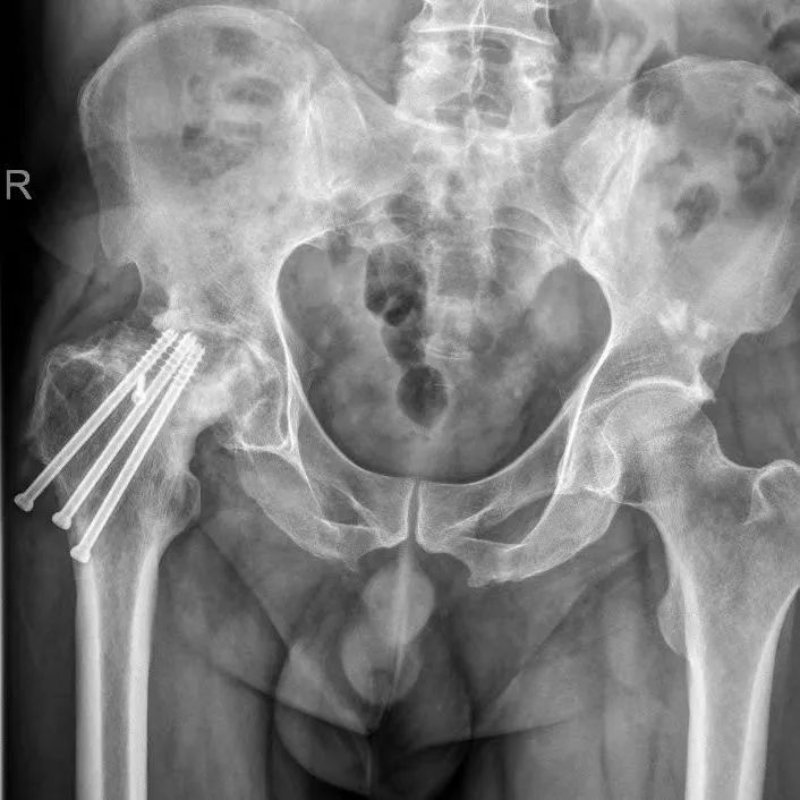

60多歲的謝阿姨,年輕時因為外傷造成右側(cè)髖關(guān)節(jié)活動受限,因為各種原因一直未得到良好的診治,就這樣右腿“瘸”了近40年,而且走起路來越來越疼。因為走路不平衡,造成了腰椎也彎曲畸形了。經(jīng)過多方尋診找到了我院骨創(chuàng)傷與關(guān)節(jié)外科陳天實主任,通過了解知道惠州市中心人民醫(yī)院博羅分院骨關(guān)節(jié)科可以完成此類手術(shù),便下定決心住院等待手術(shù)。完善術(shù)前各項檢查后,謝阿姨的指標(biāo)滿足手術(shù)條件。畸形了近40年的右髖關(guān)節(jié)給手術(shù)醫(yī)生提出了挑戰(zhàn),但通過AI策劃,將復(fù)雜的骨骼形態(tài)分析處理,給出了適合的手術(shù)方案,并通過數(shù)據(jù)模擬演示了關(guān)節(jié)假體需要安放的位置和角度,大大減輕了術(shù)前規(guī)劃的工作量。通過陳天實主任手術(shù)團(tuán)隊和麻醉科手術(shù)室團(tuán)隊的緊密配合下,謝阿姨的手術(shù)順利完成。術(shù)后3天謝阿姨便扶著助行器下地走路了,家里人都說:“早知道這么好效果,我們早點帶她來做手術(shù)了。”術(shù)后一個月,謝阿姨已經(jīng)可以在家做家務(wù)幫忙帶小孩子了。

文章配圖

△術(shù)前

△AI術(shù)前策劃

△術(shù)后